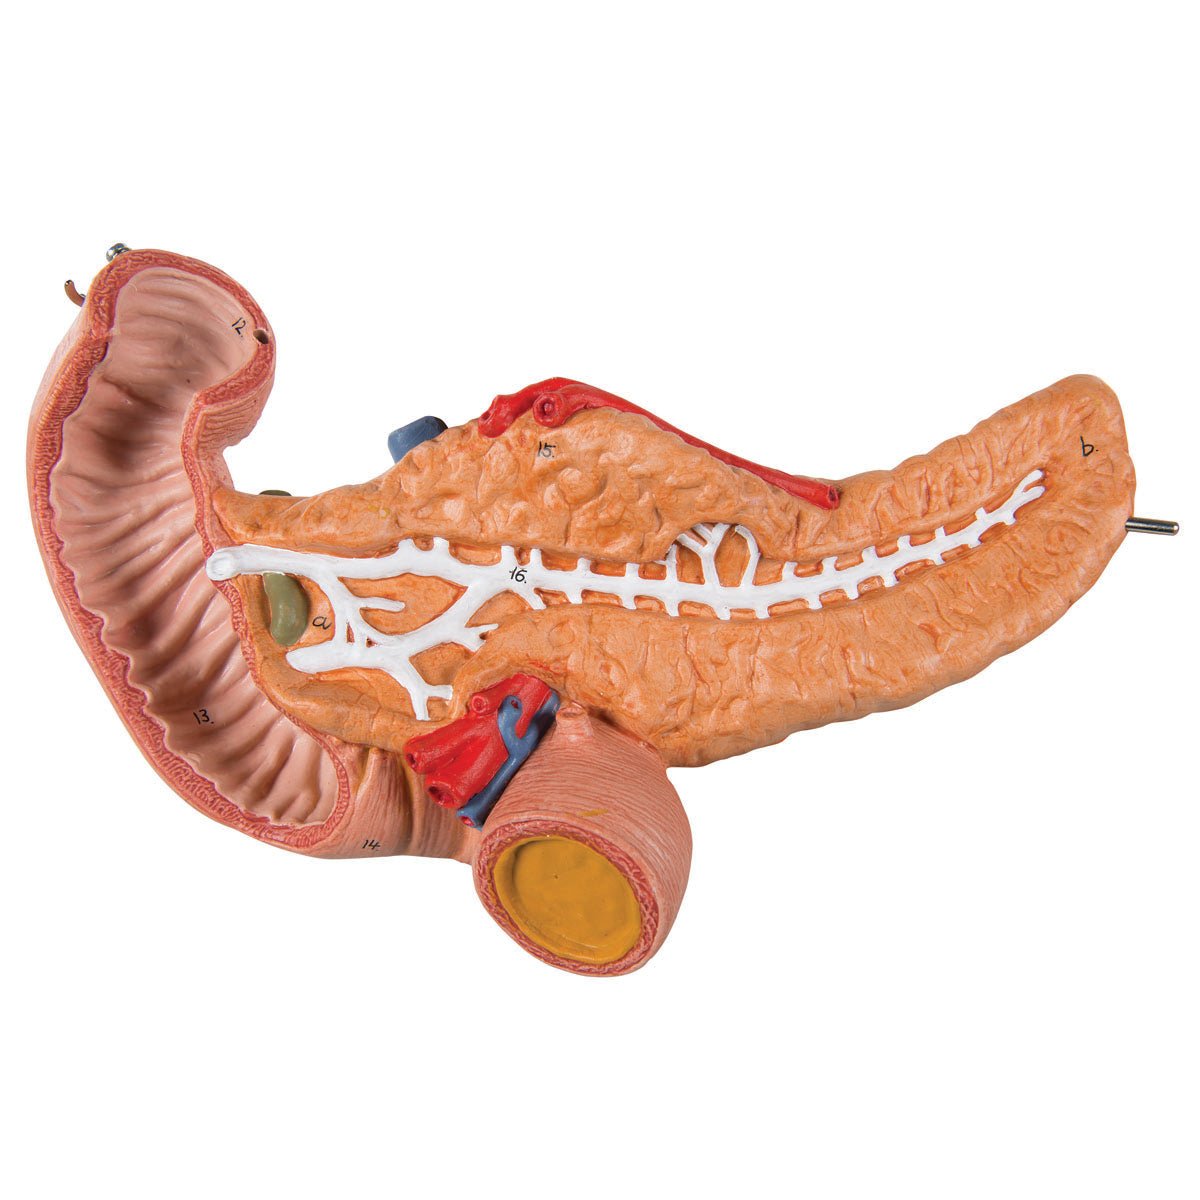

Salg af anatomiske modeller er det bærende element i eAnatomi, selvom vi også bruger mange ressourcer på at udvikle vores egne anatomiske materialer som fx plakater. Anatomiske modeller anvendes til forskellige formål og kan både vise afgrænset væv, organer samt organsystemer. Søger du en simpel model af knoglevæv eller måske en avanceret torso-model baseret på MRI teknologi, kan du finde det hele på eanatomi.com.